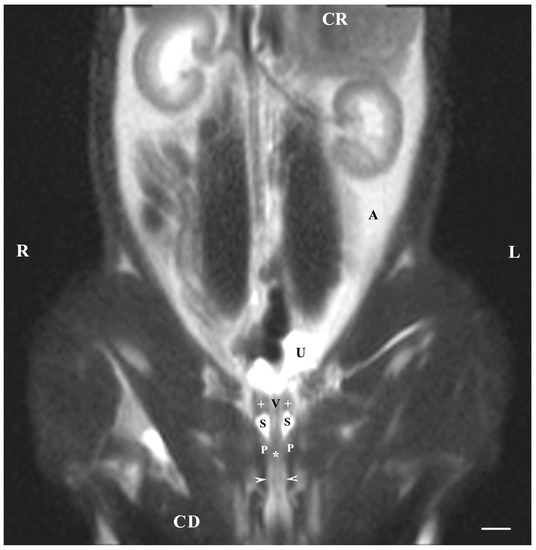

Dorsal imaging in the pelvis (at the greatest distance, dorsal to the pelvic symphysis) on T1-weighted sequences demonstrated the bulbourethral glands as homogeneous findings with low or intermediate intensity similar to that of the urethra. The intensity of the adipose tissue was used as a relative marker for the degree of tissue intensity in the studied subjects. The hypo-intense character of the glandular findings was defined as the relatively high intensity of the prostate complex and the penile root. The shape of the studied glands was oval, but their borders (capsule) were not sufficiently defined. The glands were located lateral to the caudal part of the pelvic urethra, caudal to the prostate complex and cranial to the root of the penis (Figure 4).

Figure 4. T1-weighted dorsal image of rabbit pelvis (at the level to the greatest distance, dorsal to the pelvic symphysis): R—right; L—left; CR—cranial; CD—caudal. Bulbourethral glands (white horizontal arrows), prostate gland complex (P), the pelvic part of the urethra (white star), root of the penis (black stars), and adipose tissue (A). Line—10 mm.

On the dorsal imaging of glands in T1-weighted sequences, at a relatively middle distance dorsal to the pelvic symphysis, the glandular findings could clearly be defined by the hypo-intense part of the pelvic urethra (ventromedial) and the neck of the urinary bladder (cranial). The bulbourethral glands were located caudal to the prostate complex and dorsolateral to the pelvic part of the urethra. Their shape was oval. The intensity of the bulbourethral glands was the lowest compared to that of the prostate complex. The image of the vesicular glands had the highest intensity compared to other accessory sex glands (Figure 5).

Figure 5. T1-weighted dorsal image of rabbit pelvis (at the level of the middle distance, dorsal to the pelvic symphysis): R—right; L—left. CR—cranial; CD—caudal. Bulbourethral glands (black stars), prostate complex (P), vesicular glands (black cross), the pelvic part of the urethra (white star), neck of the urinary bladder (V), and adipose tissue (A). Line—10 mm.